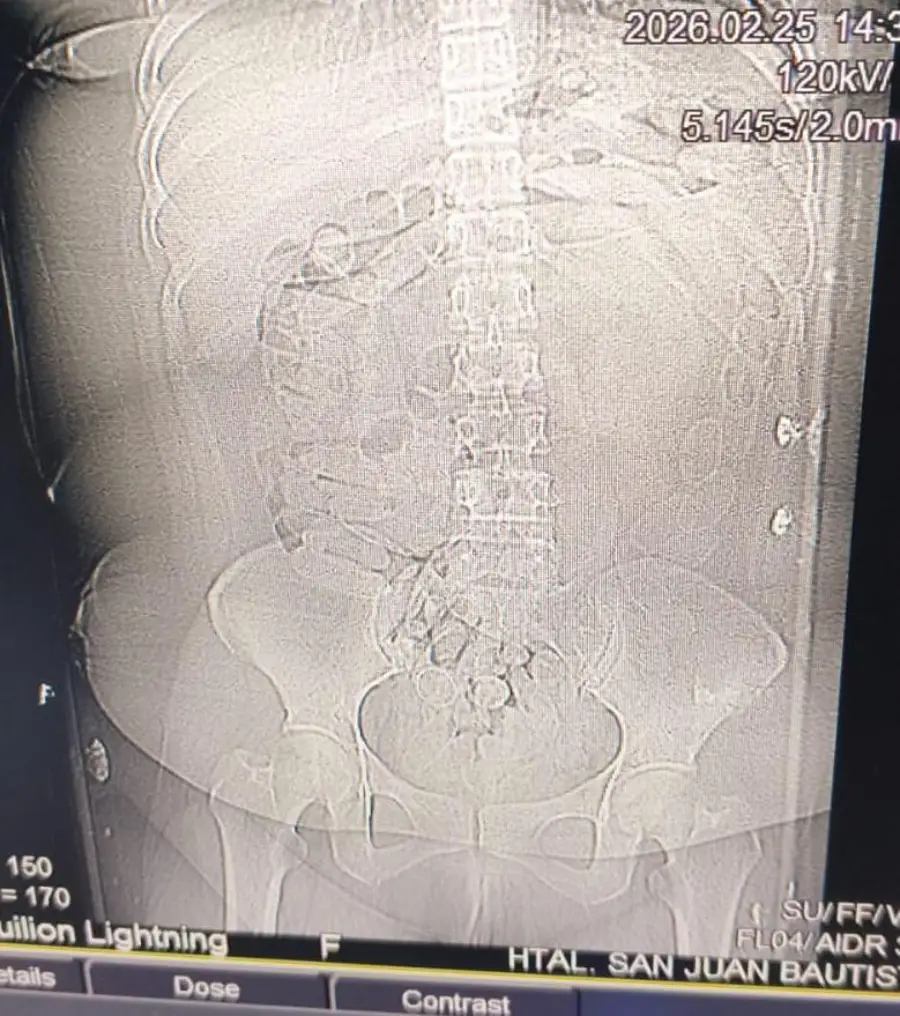

Al momento en que inspeccionaron un transporte de pasajeros con el itinerario La Quiaca (Jujuy) – Mendoza, los gendarmes detectaron a una ciudadana extranjera que presentaba indicios compatibles con el traslado de estupefacientes mediante la modalidad conocida como “camello”, por lo que se dispuso su traslado al Hospital San Juan Bautista de la ciudad de Catamarca para una evaluación médica.

Esta modalidad de transporte de droga es considerada una de las más riesgosas para la vida humana, ya que implica la ingestión o el ocultamiento de cápsulas con estupefacientes dentro del cuerpo. La ruptura de alguno de estos envoltorios puede provocar intoxicaciones severas, convulsiones e incluso la muerte, por lo que requiere inmediata intervención médica. En este caso, la mujer se descompensó durante el traslado y debió ser asistida de urgencia por personal de salud.

Tras los estudios correspondientes, se constató la presencia de cuerpos extraños en la zona abdominal y en la cavidad genital. Como resultado del seguimiento médico, se confirmó la evacuación de 90 cápsulas.

La sustancia contenida en los envoltorios era de color blancuzco y, al ser sometida a la prueba de campo Narcotest, arrojó resultado positivo para cocaína, con un peso total de 1 kilo 069 gramos.